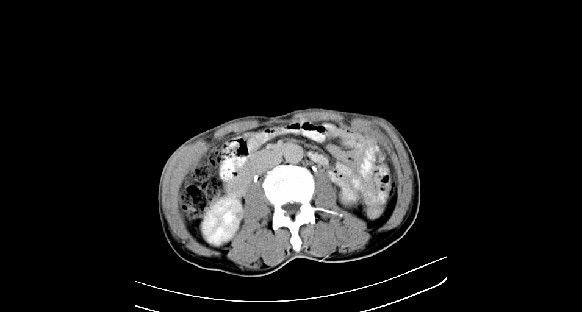

男性,70岁,体检b超发现左肾占位,请各位战友发表一下观点

左肾有两个病灶,且较大的病灶内可见点状钙化灶,增强扫描边缘也是呈渐进性强化,中央部分未见明显强化